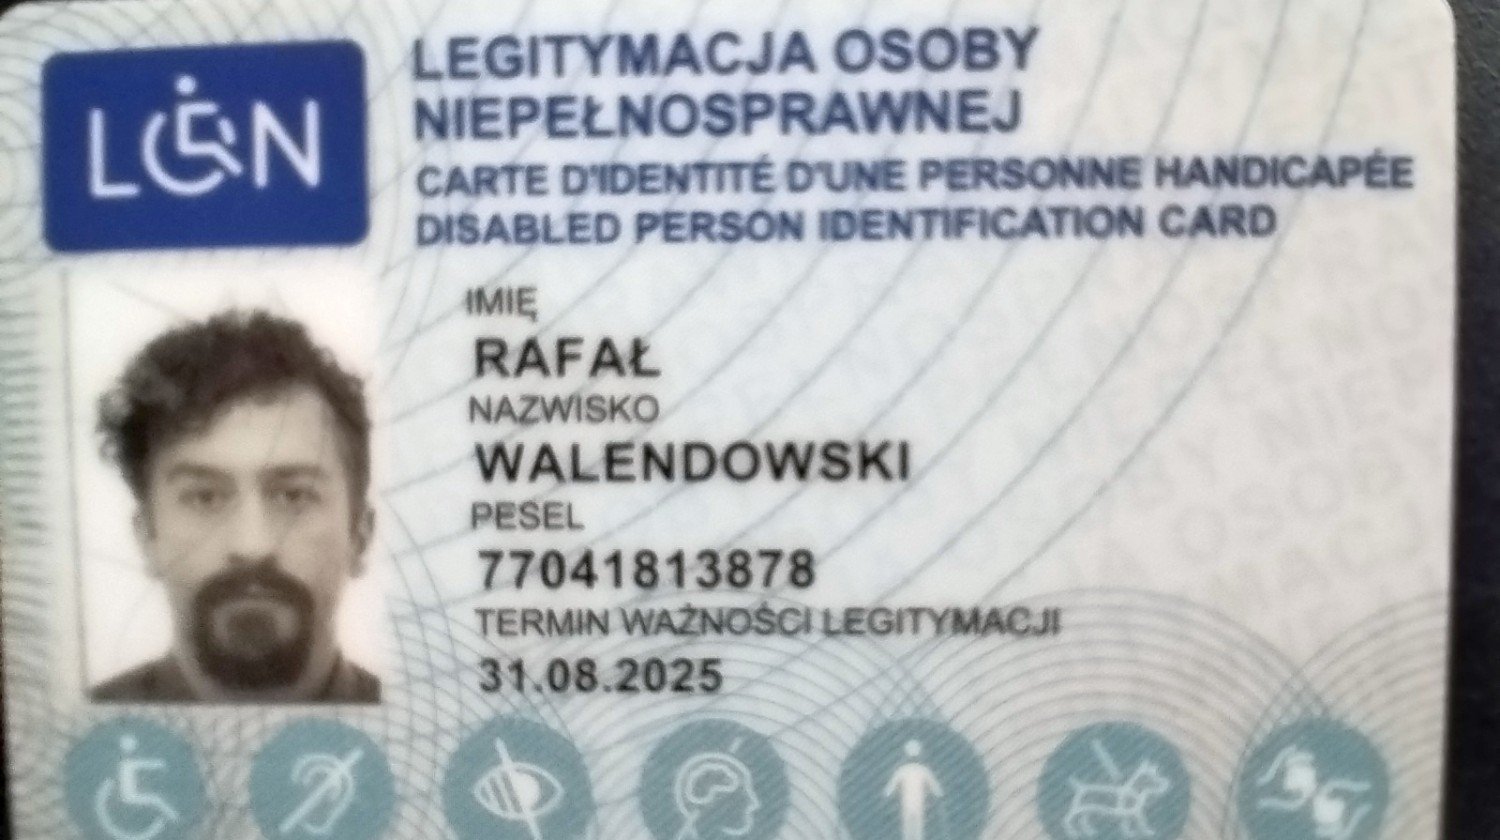

Mam 48 lat. Po studiach otworzyłem własną działalność i brałem w dzierżawę sklepy w Oleśnicy (w sumie 4), inwestowałem w nie technologicznie (włącznie z dużymi remontami), brałem kredyty na inwestycje i rozwój. Wszystko było OK..., ale 4 stycznia 2023 r. potrącił mnie na przejściu dla pieszych samochód. Teraz mam orzeczenie o niepełnosprawności.

Minęły ponad 2 lata od wypadku. Orzeczenie lekarza orzecznika ZUS z dnia 07.02.2025 r. - niezdolny do pracy na kolejne 6 miesięcy. Mogę prawie normalnie chodzić (nadal trwa rehabilitacja) i żyć. Jeszcze leczę moją potłuczoną głowę (wielkie podziękowania dla Uniwersyteckiego Szpitala Klinicznego im. Jana Mikulicza-Radeckiego we Wrocławiu - "cudotwórcy"; byłem tam 15 dni), dłużej dają znać o sobie powikłania po obrażeniach głowy - leczę się psychiatrycznie. Po wypadku zlikwidowałem działalność (dawałem pracę 19 osobom), pozostały długi finansowe, nie miałem jak zarabiać na koszty, kredyty (ok. 120 tys.) które z czasem są coraz większe (żaden ze klepów nie był moją własnością). Chciałbym znowu spróbować własnych sił z działalnością, jednak zaległości w opłatach i spłatach uniemożliwiają mi zdobycie własnych (pożyczonych) środków finansowych. Bardzo chciałbym znowuż wrócić do aktywności zawodowej jako przedsiębiorca. Mając własną działalność pomagałem ludziom potrzebującym pomocy - ile tylko mogłem. Teraz sam potrzebuję pomocy. Liczę na dobroć serc ludzkich. Za każdą wpłatę bardzo dziękuję.